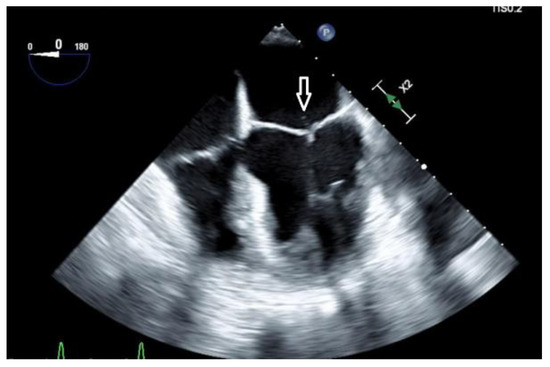

Introduction: The annual incidence of infective endocarditis (IE) is 3–9 cases per 100,000 in developed countries and most cases are due to staphylococci and streptococci. IE due to Gram-positive anaerobic cocci (GPAC) is very rare. Case report: We present a case of a [...] Read more.

Introduction: The annual incidence of infective endocarditis (IE) is 3–9 cases per 100,000 in developed countries and most cases are due to staphylococci and streptococci. IE due to Gram-positive anaerobic cocci (GPAC) is very rare. Case report: We present a case of a 38-year-old female with Anaerococcus hydrogenalis bacteremia and infective endocarditis of the native mitral valve. She presented with fever, chills, and abdominal pain. A computed tomographic scan of the abdomen showed splenic abscesses. Blood cultures and broad-range PCR from the splenic abscess sample were negative. Transthoracic echocardiography showed a mobile filamentous structure on the atrial side of the anterior mitral leaflet which was suggestive for infective endocarditis. Karius test (cell-free microbial DNA testing) showed Gram-positive anaerobic cocci Anaerococcus hydrogenalis. She was successfully treated with antibiotics. Conclusions: In cases of infection with fastidious organisms like GPACs, the use of next-generation sequencing (NGS) can allow the correct identification of culprit pathogens and streamlined treatment. Full article

Show Figures

Figure 1